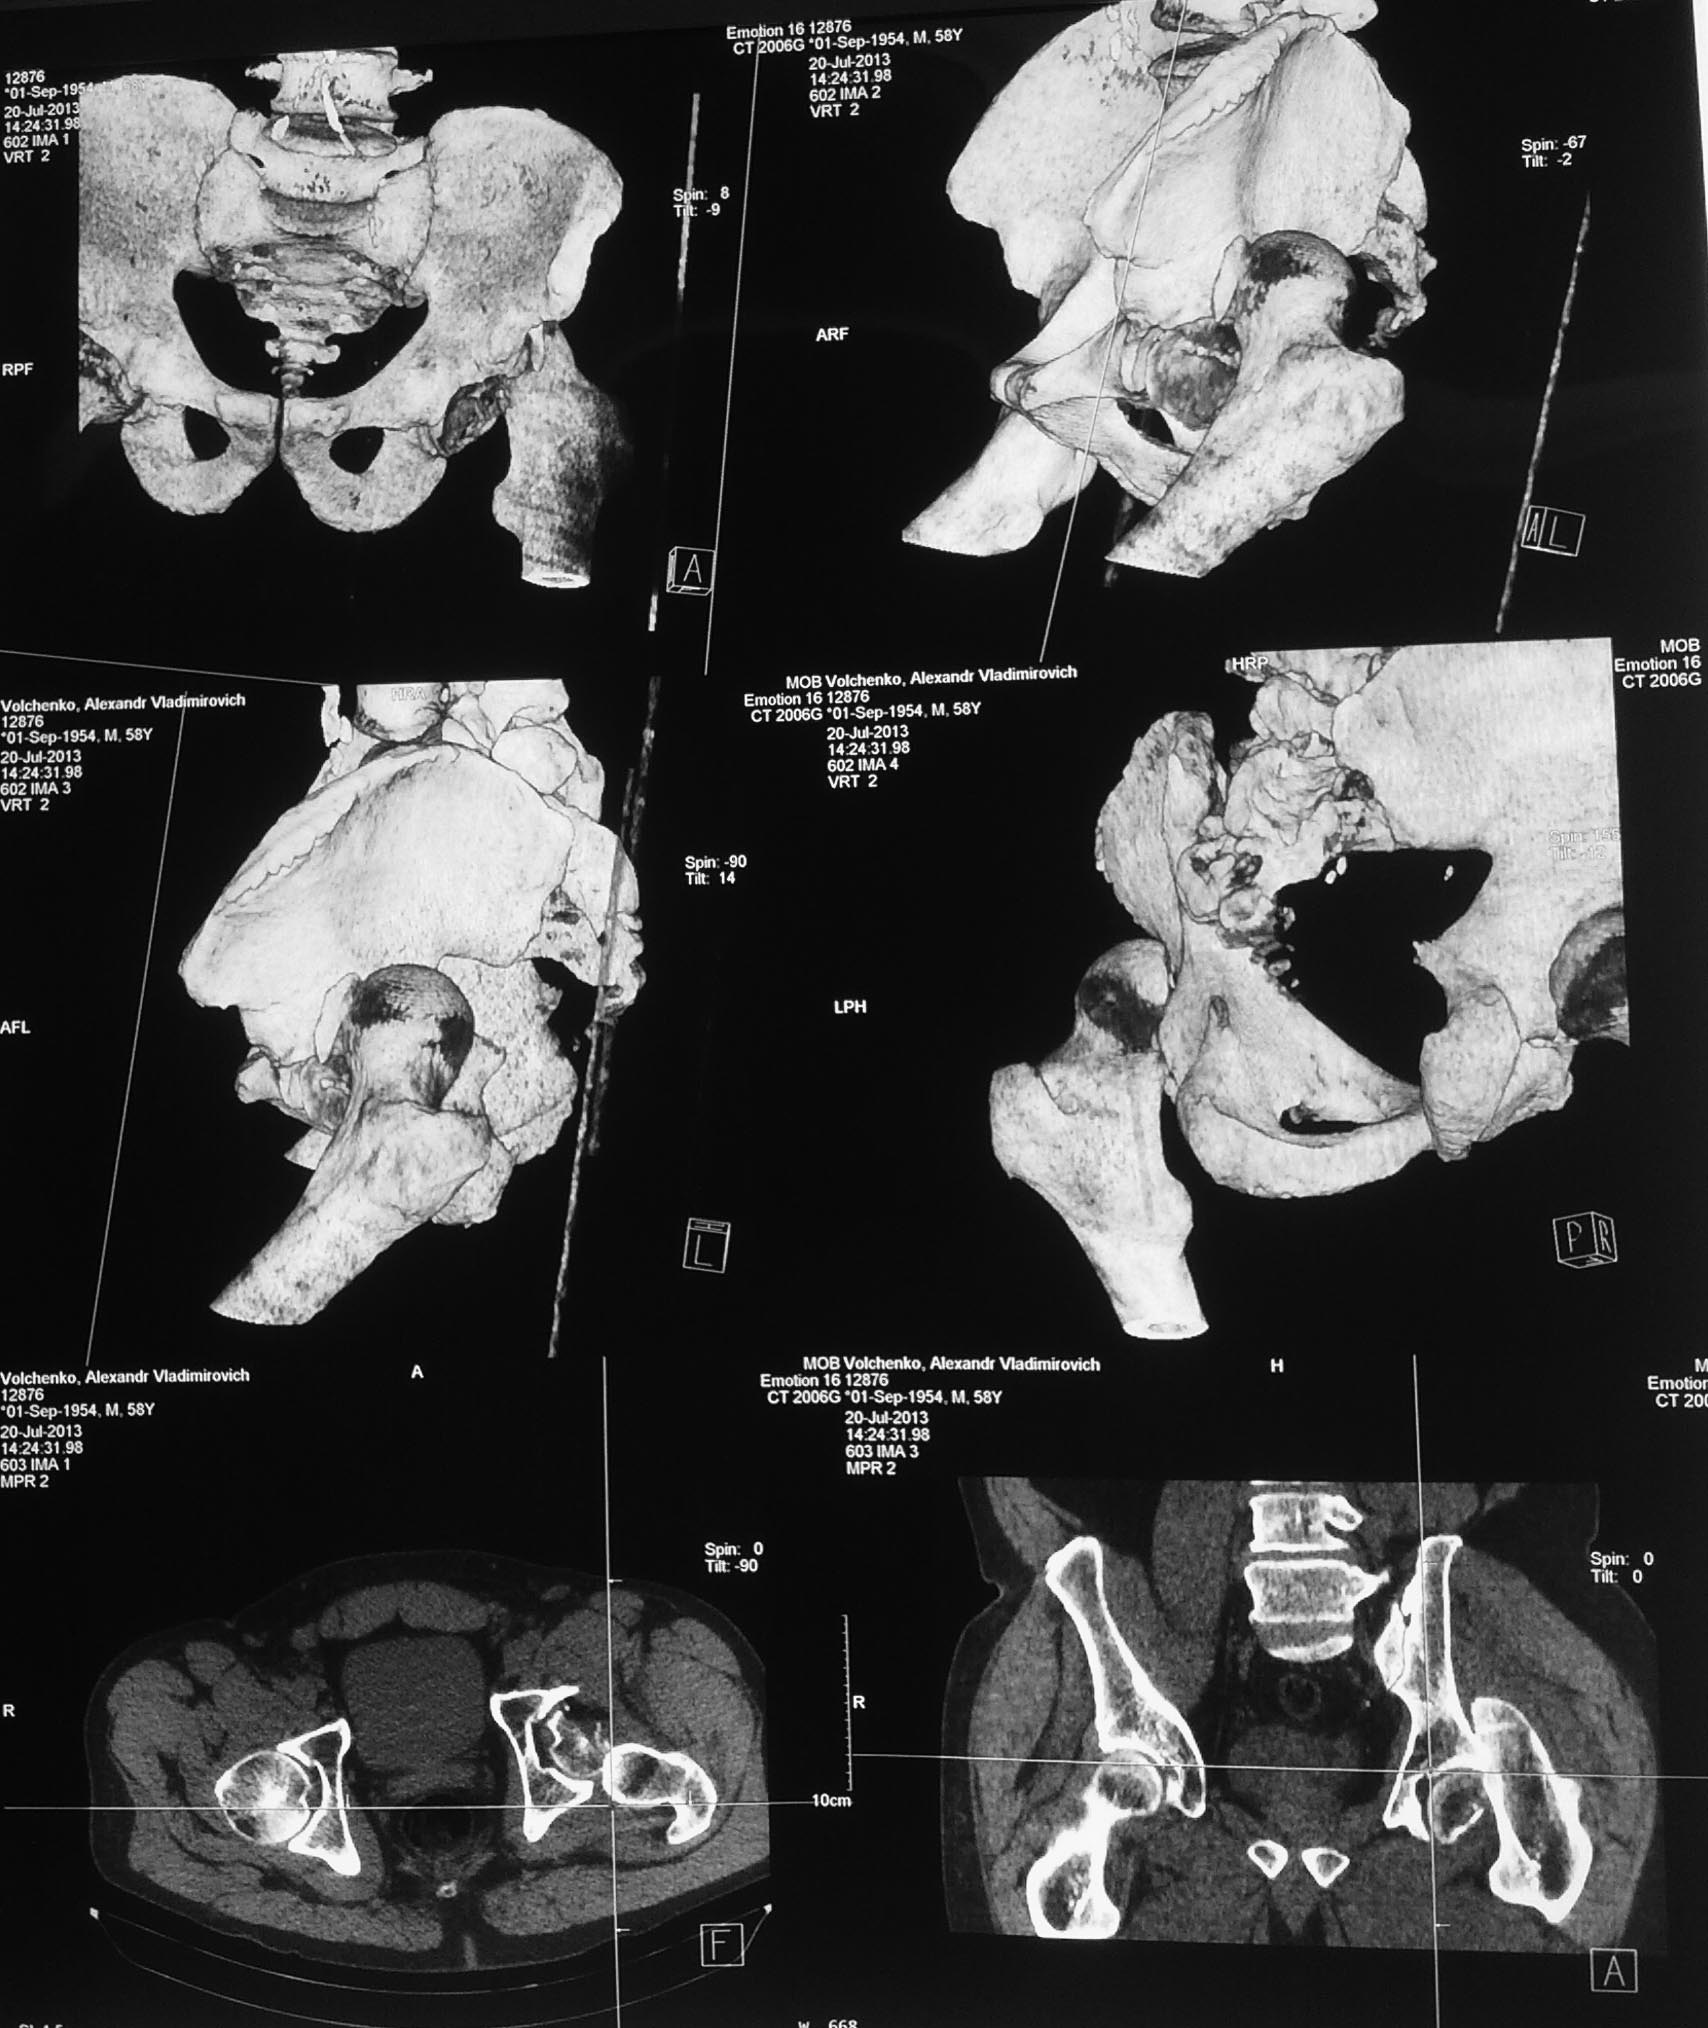

[Ortho] Перелом головки бедра, заднего края вертлужной впадины.

Доступ с остеотомией большого вертела. Очень часто приходится вывихивать

головку бедра. Можно оцень крообращение и прогноз. В любом случае синтез

а там как кривая выведет. Синтез головки и заднего края винтами. Если

разрыв губы, либо малый фрагмент, то фиксация анкерами. Необходимо

оценть стабильность на ЭОП.